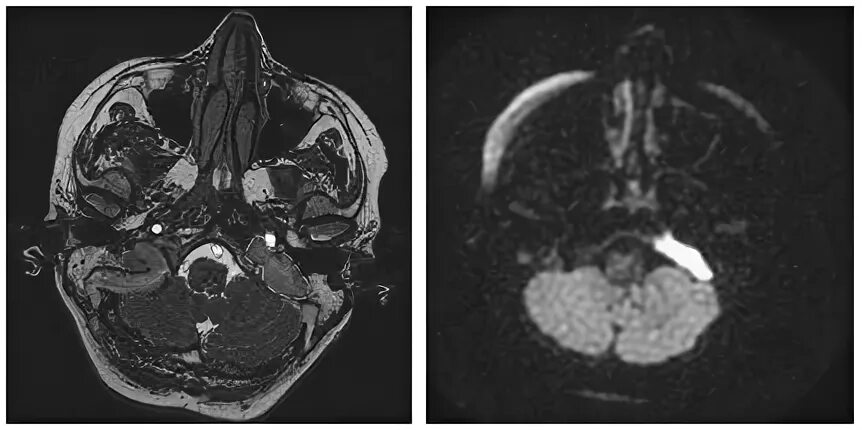

Мрт височных костей в режиме dwi